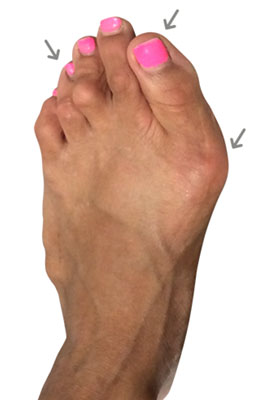

Minimally Invasive Bunion Surgery featuring the miniBunon™ System and Tailors Bunionectomy

Melissa is a 32-year-old businesswoman who could not be off her foot post-surgery, yet she had a severely painful bunion. We performed our miniBunon™ System (our trademarked minimally invasive bunion surgery) and had a dramatic correction with no downtime. Melissa continued to work after her bunion surgery and was back in shoes and full activity at 5 weeks. Melissa could not believe the results of her Bunionectomy resulting in no bony bump, no scar and amazing motion. “After” picture taken immediately following surgery. Note the bunion and bunionette (Tailor’s bunion) in the before picture.